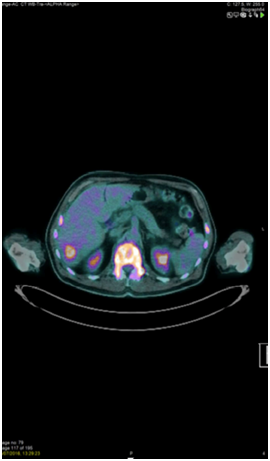

A whole-body PET-CT scan was performed. This revealed FDG avidity on the left side of the neck with further abnormal foci noted within the left tonsillar bed, lateral left side of the tongue base and lower cervical node chain (Figure 2). It also showed tracer uptake of the skull vault, skull base, mandible, all of the vertebral bodies, both humeri, both scapulae, multiple ribs, sternum, pelvis and both proximal femora. At these sites there was evidence of mixed lytic and sclerotic disease. No encroachment of the spinal cord was seen. Three small FDG avid intrahepatic lesions were also noted and there was a small FDG avid lower right-sided para-aortic node also (Figure 3). Spleen, kidneys, adrenals, bowel and prostate were noted to be normal. Laboratory panel showed a haemoglobin of 81g/dL, white cell count of 7.2, platelets of 5 and an LDH of 1057. Other markers, including calcium, were within the normal range. A blood film showed a leucoerythroblastic picture with normocytic, normochromic red cells, some polychromatic cells, thrombocytopaenia, a left neutrophil shift, myelocytes and occasional blast cells. Lymphocytes were small and mature.

Figure 2 18FDG PET confirming the head and neck primary plus multiple spinal, Sternal, Pelvic, Humeral and Extra-osseous metastases (including liver).